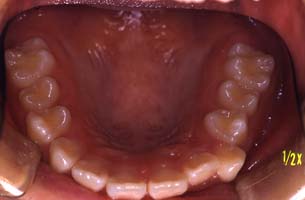

下顎

(ミラー像) | | | | | |